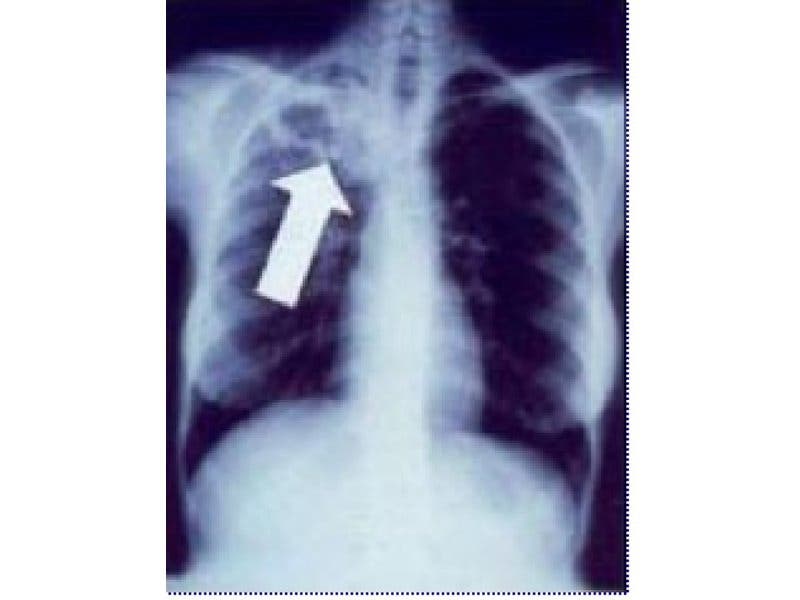

Tuberculosis can affect a person’s lungs, brain, kidneys and spine, according to the Centers for Disease Control. It can be fatal and is spread through the air, such as when a person coughs or sneezes. It is treatable with medications.